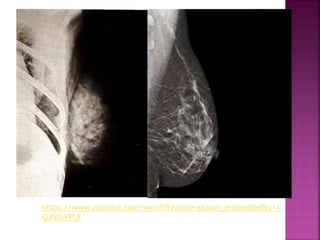

MAMOGRAFIA

AULA Nº1

Profª JULIANA TRIBIOLI MIZUSAKI